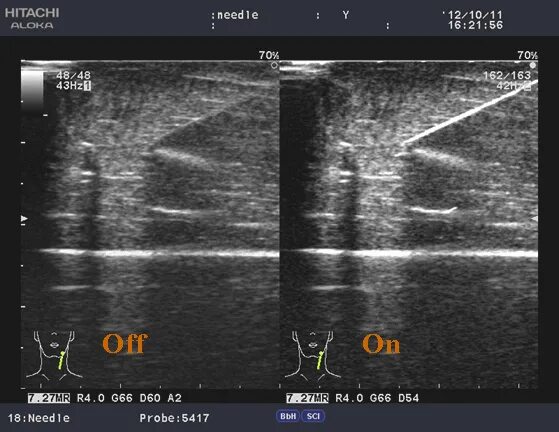

Ультразвуковая система навигации